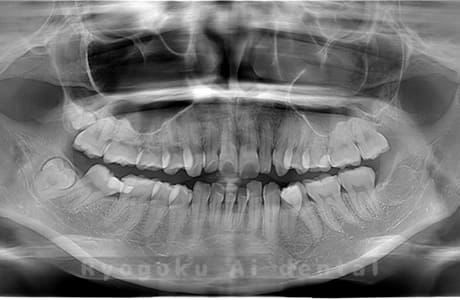

Case01

- 原因

- 水平埋伏智歯

- 治療内容

- 下顎の水平埋伏智歯を抜歯

<リスク・副作用>

手術後は痛み、腫れ、痺れなどの副作用が生じる場合があります。